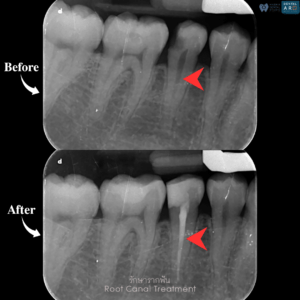

รักษารากฟัน

คือ การรักษาฟันที่เกิดการอักเสบและติดเชื้อภายในโพรงประสาทฟัน และเนื้อเยื่อรอบปลายรากฟัน อันมีสาเหตุมาการอักเสบและติดเชื้อภายในรากฟัน โดยทันตแพทย์จะทำการทำความสะอาดและใส่ยาในคลองรากฟัน และทำการอุดรากฟันเป็นขั้นตอนสุดท้าย การรักษารากฟันจะช่วยเก็บรักษาฟันให้สามารถคงอยู่ในช่องปากต่อได้ โดยไม่ต้องถอนฟันและไม่ต้องใส่ฟันทดแทน